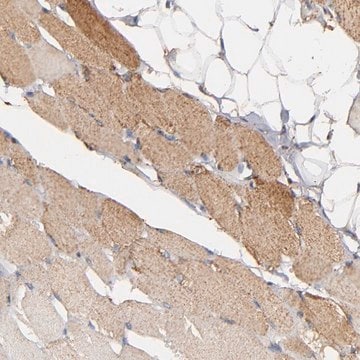

Anti-SOD2 antibody produced in rabbit

Anti-Superoxide dismutase [Mn], mitochondrial precursor antibody produced in rabbit, Anti-IPO-B, Anti-MNSOD, Anti-Superoxide dismutase 2, mitochondrial